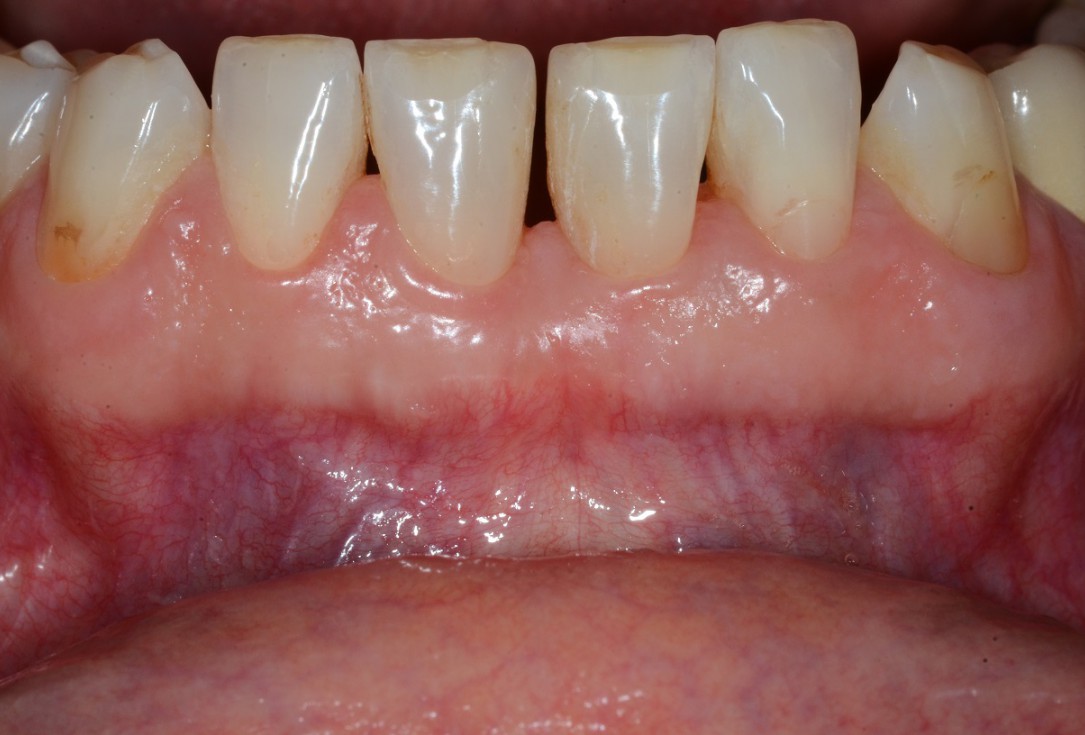

01/13 - Baseline clincial situation and pre-surgical probing.

Wide intrabony defect treated with the modified papilla preservation flap in conjunction with Straumann® Emdogain® and autogenous bone - Dr. B. Molnar